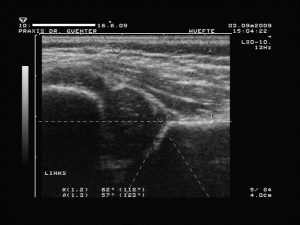

1. Linie (Grund- oder Basislinie bzw. -tangente: vom obersten Punkt der Fixierung des Perichondriums (so genannter Z-Punkt) am Ilium tangential nach distal bzw. ggf. eine Hilfslinie parallel am Rand der Schallauslöschung, welche auch schräg zu Bildkante sein kann!)

2. Linie (Pfannendachlinie bzw. -tangente: an Unterrand des Ileum und tangential an Unterkante des knöchernes Pfannendaches bzw. Erker)

und 3. Linie (Ausstell(ungs)linie: vom Umschlagspunkt der Pfannenkonkavität zur Konvexität durch die Mitte des Labrum).- Dadurch entstehen messbare Winkel (kranial zwischen Linie 1 und 2 der a-Winkel sowie kaudal zwischen 1 und 3 der b-Winkel) für die

Graduierung

- nach Graf mit dem Sonometer

Typ IIa+, a–, b

verzögerte knöcherne Entwicklung bzw. Reifungsstörung in Abhängigkeit zur 12. Lebenswoche (Unterscheidung a vor und b nach der 12. LW) mit (+) oder ohne (-) Entwicklungs- bzw. Wachstumstendenz (knöcherner Formgebung: ausreichend (bis zur 12. Wochen) oder mangelhaft (ab der 12. Woche), Erker: rund und Labrum: breit übergreifend, a-Winkel: 50 – 59° (bei „+“ größer werdend), b-Winkel: < 77°)